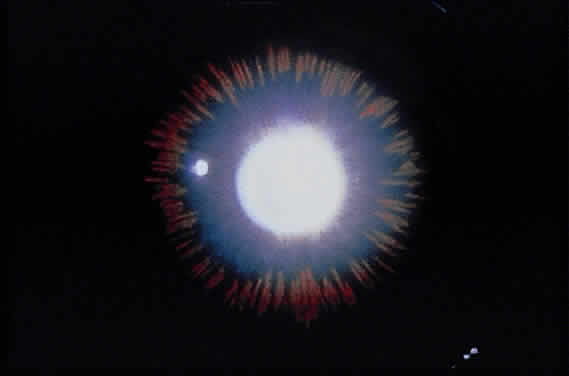

Deposition of exfoliative material on the anterior lens surface is the most commonly recognized feature of XFS and usually is best appreciated after pupillary dilation.43 A bull's-eye pattern generally is seen in which a translucent central zone and a granular peripheral zone of deposition are separated by an intermediate clear zone (Fig. 1). The translucent central zone of exfoliative material varies in diameter and may exhibit curled edges. In approximately 20% of patients with exfoliation, the central zone may be absent.38 The intermediate clear zone presumably results from lens contact with movement of the iris. The granular peripheral zone, which may be subtle but invariably is present in XFS, generally exhibits a well-delineated inner border and often shows numerous radial striations (Fig. 2). Occasionally, a bridge of exfoliative material may cross the clear zone to join the central zone and the granular peripheral zone.38,44

Fig. 2. Granular peripheral zone with well-defined inner border and numerous radial striations.